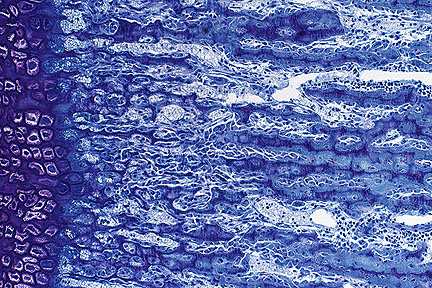

Cleft formation, fibrillation, and formation of chondrones in the articular cartilage of a thoroughbred horse with osteochondrosis of the cervical vertebra (HE, 100X, 87K)

Marked chondrone formation secondary to osteochondrosis in the articular cartilage of a horse. (HE, 400X, 77K)

88-2757: Morphologic diagnosis - Necrosis and cleft formation at articular - epiphyseal complex with resorption and fibrous replacement of subchondral bone. Name the disease - osteochondrosis. Etiology - unknown. 89-42: Morphologic diagnosis - Necrosis and cleft formation within epiphyseal and articular cartilage with chondrone formation and fibrillation. Name the disease - osteochondrosis with secondary degenerative joint disease. Etiology - unknown.

Slides from both cases were needed to achieve the number of slides required and it is not intended that the lesions be compared and correlated with clinical signs. Most slides are from the control horse to emphasize the nature of lesions that can occur symptomatically. In this particular study, severity but not frequency of lesions of osteochondrosis in cervical vertebrae was greater in horses with cervical stenotic myelopathy than in the controls. The frequency and severity of osteochondrosis in the appendicular skeleton were both greater in horses with cervical sites of compression but compression also occurred at sites with no lesions. Most lesions of osteochondrosis in cervical facets have areas of retention of growth cartilage with variable invaginations. The lesion present on these two slides represents necrosis and cleft formation without apparent cartilage retention. This is considered a form of osteochondrosis and has been associated with copper deficiency, zinc excess and cadmium excess in horses. The role of these deficiencies in the current cases in unknown. The resorption of subchondral bone and fibrosis in 88-2757 and the chondrone formation and fibrillation in 89-42 are considered secondary.

AFIP Diagnosis: Cervical vertebra, articular facet: Necrosis and cleft formation, focally extensive, moderate, with chondrone formation and subchondral fibrosis, Thoroughbred, equine.